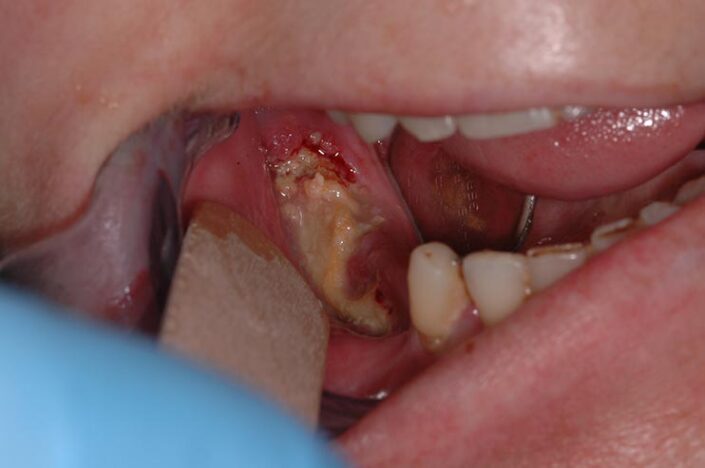

Osteonecrosi del mascellare superiore di destra

MRONJ e Definizione

“L’osteonecrosi delle ossa mascellari associata a farmaci (MRONJ) è un evento avverso farmaco-correlato, caratterizzato dalla progressiva distruzione e necrosi dell’osso mandibolare e/o mascellare di soggetti esposti al trattamento con farmaci per cui sia accertato un aumentato rischio di malattia, in assenza di un pregresso trattamento radiante”.

Questa definizione si basa su questi 3 parametri:

- trattamento in corso o precedente con agenti antiriassorbitivi o antiangiogenici

- osso mascellare esposto o osso che può essere sondato attraverso una fistola intraorale o extraorale nella regione maxillo-facciale che ha per- resistito per più di 8 settimane

- nessuna storia di radioterapia o metastasi delle ossa mascellari [11]

Segno clinico maggiore:

- Esposizione osso necrotico (Cavo orale)